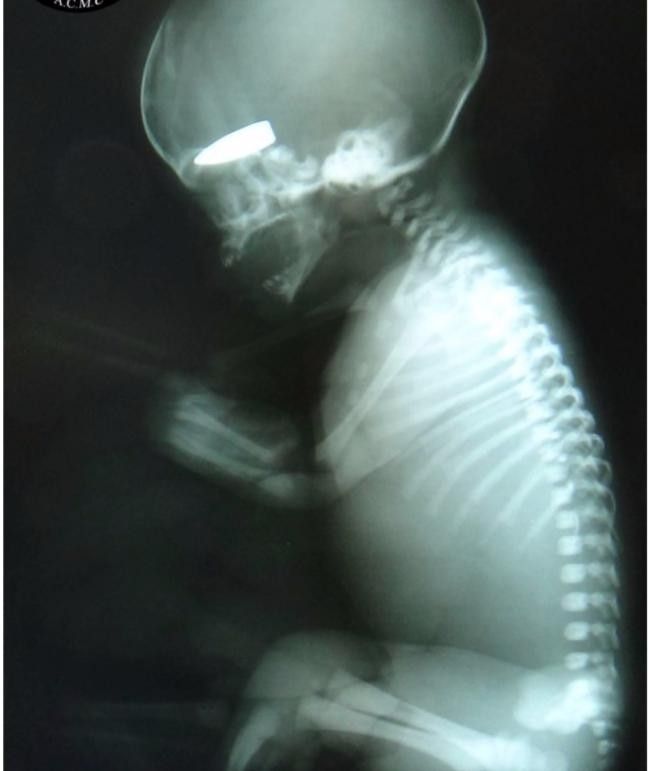

Dhe për të “argumentuar” këtë janë publikuar fotografitë e 15 sirianëve të vegjël, shumica e të cilëve në gjendje të rëndë. /Telegrafi/